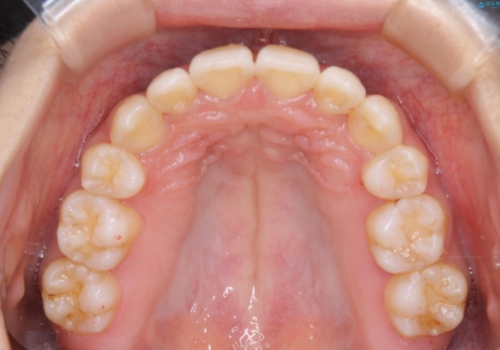

- 元々は海外でワイヤー矯正を行っていたが、コロナ禍で海外への往来が難しくなり、治療を中断せざるを得なくなってしまった方です。

ご本人のご希望により、インビザラインによる治療を行いました。

ブラケット除去直後に目立っていた下顎前歯部の大きなブラックトライアングルもあまり目立たなくなり、大変喜んでいただけました。